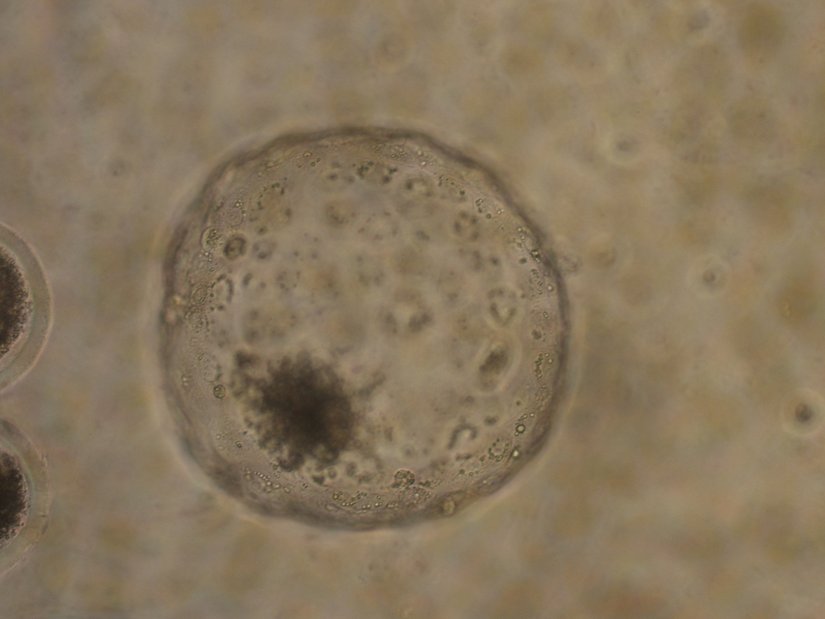

Klasik tüp bebek tedavilerinde elde edilen embriyolar 2-3 gün laboratuvarda izlendikten sonra, kalitesi yüksek olduğu düşünülen 1 ya da en fazla 2 tanesi anne adayının rahmine transfer edilir. Yani embriyolar laboratuvarda 3-7 gün kültürlenmeye bırakılabilir ve genellikle 3. gün transfer yapılır. Embriyoların 5. güne kadar bu kültür ortamında tutulup, 5. güne kadar dayanabilenlerin transfer edilmesi ise “blastosist transferi” olarak adlandırılır.

Blastosistler, en az 5 günlük bir gelişimden sonra transfer edilen, bu bakımdan da en güçlü oldukları düşünülen embriyolardır. Tıbbi teknolojideki ve tüp bebek tedavilerindeki ilerlemeler, yeni gelişmeler, embriyoların transfer işleminden önce blastosist aşamasına getirilmesini kolaylaştırmış ve blastosist transferi de tüp bebek tedavisindeki başarı şansını artırmıştır.

Tüp bebek tedavisinde erken aşama embriyolar yerine blastosistlerin transfer edilmesi, embriyonun kalitesini izlemek için daha fazla zaman sağlar. Bu sayede de tüp bebek uzmanın transfer için en uygun embriyoları seçmesi ve implantasyon başarısı şansını arttırması mümkün olabilir.

Blastosist transferi, “doğal” bir hamilelik sürecini, klasik tüp bebek tedavisine göre daha yakından taklit eder. Çünkü korumasız cinsel ilişki ile doğal olarak döllenmiş bir embriyo, gelişiminin 5. gününde uterus için fallop tüplerinden bırakıyor olur ve uterusun astarı bu bölgeyi implantasyona en elverişli duruma getirir. Yani aslında blastosist transferi hem embriyo kalitesinin daha yüksek olması hem de rahim duvarının tutunma için en elverişli hale gelebilmesi ve bunlardan dolayı da implantasyon başarısının artması için önemlidir.